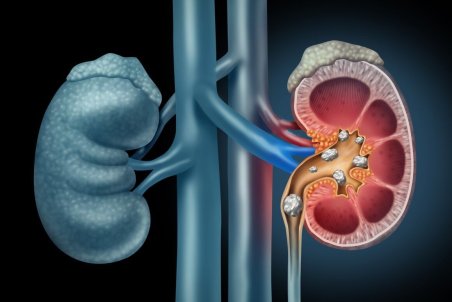

سنگ کلیه جسم سختی است که از موادشیمیایی در ادرار تشکیل شده. انواع متعددی دارد،اما همه دارای علائم مشابهی هستند که می تواند بسیار دردناک باشند،به ویژه اگر سنگ کلیه به مرور زمان رشد کرده باشد.

یکی از مشکلات کلیوی رایج سنگ کلیه می باشد که از مواد معدنی و نمکی در دستگاه ادراری تشکیل می شود. یکی از راه هایی که مورد توجه افراد بسیاری قرار می گیرد استفاده از داروهای گیاهی برای سنگ کلیه می باشد که در این مقاله به معرفی آنها می پردازیم.

روشهای درمان سنگ کلیه شامل مصرف دارو، سنگ شکن برون اندامی (ESWL) و اورتروسکوپی میشود.

تجمع بیش از حد املاح در کلیهها میتواند منجر به تشکیل سنگهایی به شکل کریستال شود که اگر دفع نشوند، میتوانند عوارضی چون عفونت یا آسیبهای کلیوی را بهدنبال داشته باشند.

معمولاً سنگهای کلیه کوچک، بدون بروز علائم و مشکلات خاصی دفع میشوند اما سنگهای بزرگتر در مجاری ادراری لانه میکنند و منجر به درد میشوند؛ اگر این سنگها دفع نشوند، میتوانند عوارضی چون عفونت یا آسیبهای کلیوی را بهدنبال داشته باشند.